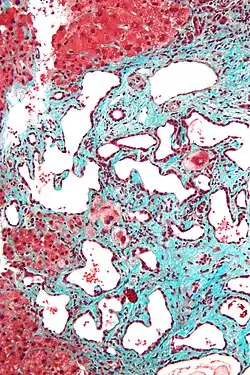

Micrograph of a bile duct hamartoma. Trichrome stain. Intermediate magnification -

Micrograph of a bile duct hamartoma. Trichrome stain, high magnification -

Low magnification micrograph of a bile duct hamartoma. Trichrome stain. -